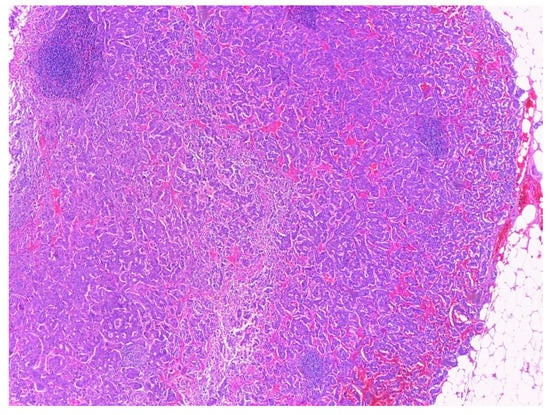

2.4. Histopathological Exam

| Sample | Sample | Sample 1 | Sample 2 | Sample 3 | Sample 4 |

| Aspect | Tumor proliferation with cells containing round, oval, pleomorphic nuclei, and fine granular chromatin. Proliferation covered the entire section and caused partial ulceration of the mucosa that crosses muscular propria layer and extends into the peripancreatic adipose tissue with discrete infiltration of pancreatic acini. Infiltration was clearer after synaptophysin labeling. | Tumor proliferation with atypical cells, fasciculate disposition, elongated nuclei, discrete nucleoli, and pale eosinophilic cytoplasm. The apparent origin of the tumor is muscularis propria | Small intestine sample with tumor proliferation, composed of cells with fascicular disposition, elongated and non- pleomorphic nuclei, pale eosinophilic cytoplasm, rare epithelioid cells. The apparent origin of the tumor is muscularis propria | Sample muscle proliferation with tumor proliferation composed of cells without atypia, fascicular disposition, elongated nuclei, discrete nuclei, and pale eosinophilic cytoplasm | Sample muscle proliferation with tumor proliferation composed of cells without atypia, fascicular disposition, elongated nuclei, discrete nuclei, and pale eosinophilic cytoplasm |

| Tumor cells | CgA-positive SPY-positive Ki67-reduced, maximum 2% | c-kit-positive DOG1 positive SMA-negative | c-kit-positive DOG1 positive SMA-negative CgA-negative | c-kit-positive SMA-negative | c-kit-positive SMA-negative |